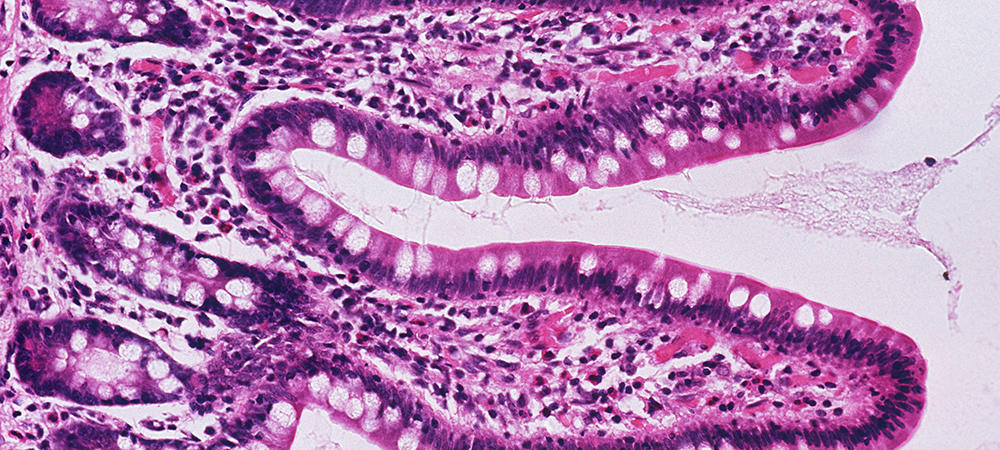

Mycobacterium avium subsp. paratuberculosis is the causative organism of Johne′s disease (or paratuberculosis), a debilitating chronic gastroenteritis in ruminants. Animals typically become infected by the fecal-oral route in the first few months of life. The chronic wasting and profuse diarrhea that characterize clinical paratuberculosis are not usually observed until three or more years following infection. Paratuberculosis is prevalent in domestic animals worldwide and has a significant impact on the global economy, including the Canadian economy.